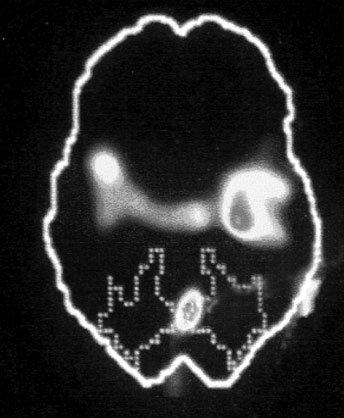

А. Правая лимбическая область

Иллюстрация к книге — Тело помнит все [i_002.jpg]

Изображение мозга в процессе переживания травмы. Светлые пятна в лимбической коре (А) и зрительной коре (Б) соответствуют повышенной активности мозга в этих участках. На снимке (В) видна значительно пониженная активность речевого центра мозга.

На снимках были некоторые сбивающие с толку точки и цвета, однако самая яркая область активации мозга – большое красное пятно в правом нижнем центре мозга, известном как лимбическая область, или эмоциональный мозг, – никакого удивления не вызывала. Мы уже знали, что сильные эмоции активируют лимбическую систему, в особенности участок внутри нее, известный как миндалевидное тело.